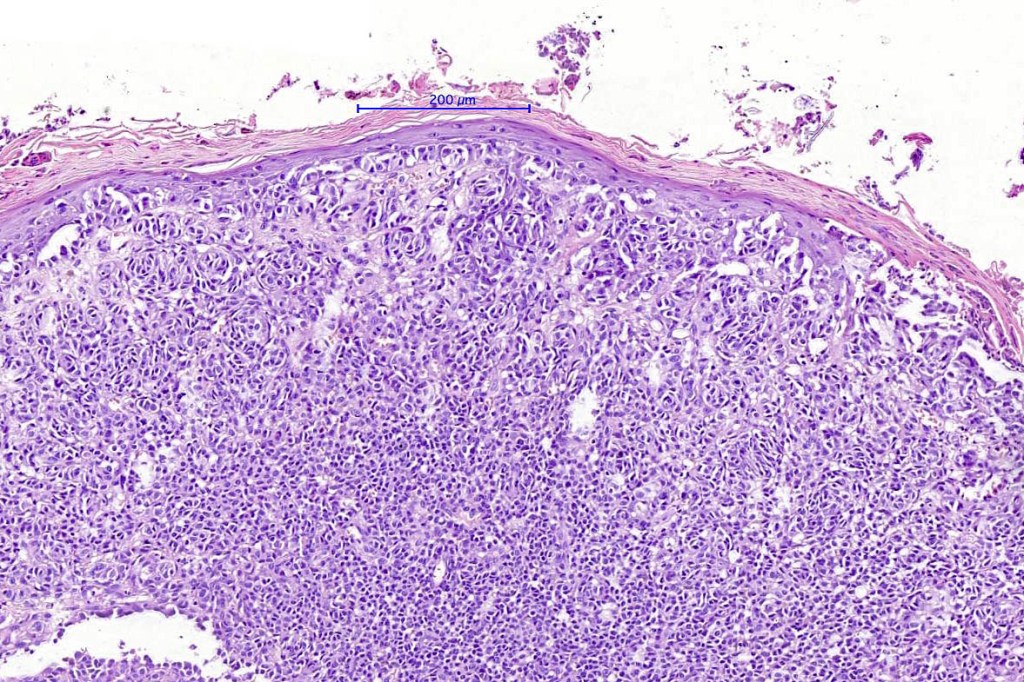

•Verrucous or dome-shaped, at low power, the lesion looks like a nevus

•Minimal or no junctional component

•Expansile nodules or diffuse

•Compression of connective tissue

•Stretched & elongated rete ridges in verrucous variants

•Subtle or not so subtle impaired maturation with depth (sometimes this is evident at scanning magnification)